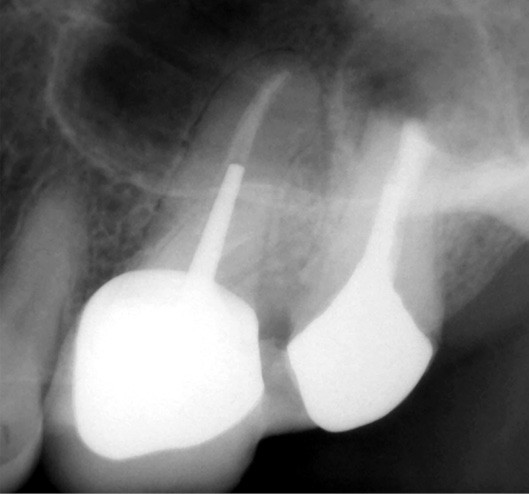

Traitement endodontique

Comme mentionné précédemment, l’insuffisance instrumentale dans la préparation canalaire n’est plus à démontrer.

Si les isthmes sont particulièrement mis en évidence au niveau des molaires mandibulaires, cela devient médicalement important au niveau des molaires maxillaires.

La diffusion bactérienne et de leurs toxines, au niveau des molaires maxillaires est à l’origine d’un grand nombre de sinusites maxillaires chroniques, d’origine dentaire. Celles-ci sont principalement causées par l’absence de traitement du deuxième canal MV, qui existe dans 90 % des cas, et il est à noter que ces deux canaux – MV1 et MV2 – sont également reliés par un isthme.

Le nettoyage des isthmes intercanalaires reste un réel problème, et semble responsable de nombreux échecs [43]. Par ailleurs, il est nécessaire d’utiliser des instruments qui évitent de propulser les débris, tant apicalement que latéralement, en obturant les entrées isthmiques avec des débris compactés.

L’utilisation d’instruments en nickel titane, tels que le XP Shaper (FKG), le Vortex blue (Dentsply) ou le Profile (Dentsply), optimise la remontée des débris et s’inscrit dans cette nouvelle philosophie. En conséquence, la combinaison XP Shaper, XP Finisher et l’irrigation avec l’Er:YAG semblent optimiser nos traitements [44,45].

Le passage du laser est répété plusieurs fois, en début, au milieu et en fin de préparation. Un protocole peut alors être proposé : 40 mJ ; 20 Hz (fig. 7). L’utilisation de biocéramiques Bioroot (Septodont) ou Total Fill R (FKG) permet de sceller le système ainsi nettoyé, en assurant une action biologique de longue durée [46] (fig. 8a à c).